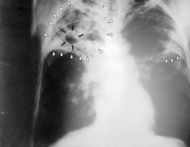

| Chest X-ray of a patient suffering from tuberculosis | ||

The typical symptoms of tuberculosis are a chronic cough with blood-tinged sputum, fever, night sweats and weight loss. Infection of other organs cause a wide range of symptoms. The diagnosis relies on radiology (commonly chest X-rays), a tuberculin skin test, blood tests, as well as microscopic examination and microbiological culture of bodily fluids. Tuberculosis treatment is difficult and requires long courses of multiple antibiotics. Contacts are also screened and treated if necessary. Antibiotic resistance is a growing problem in ( extensively) multi-drug-resistant tuberculosis. Prevention relies on screening programs and vaccination, usually with Bacillus Calmette-Guérin (BCG vaccine).

Tuberculosis can be a difficult disease to diagnose, mainly due to the difficulty in culturing this slow-growing organism in the laboratory (4–12 weeks for blood culture). A complete medical evaluation for TB must include a medical history, a chest X-ray, and a physical examination. Tuberculosis radiology is used in the diagnosis of TB. It may also include a tuberculin skin test, a serological test, microbiological smears and cultures. The interpretation of the tuberculin skin test depends upon the person's risk factors for infection and progression to TB disease, such as exposure to other cases of TB or immunosuppression.